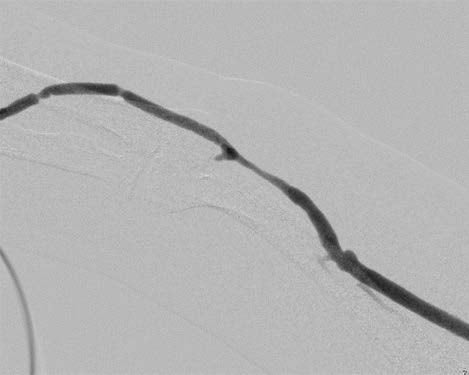

人工血管に 5-0 ナイロンでマットレス縫合をかけてその中心部を穿刺しシースを挿入して造影(図1)を行ったところ、人工血管 - 静脈側吻合部に有意狭窄を認めた。0.018 インチガイドワイヤー を通過させ同部をPTA バルーンカテーテル(カッティング型)でwaist が消失するまで拡張し狭窄を解除した(図2)。バルーン拡張術後の造影で同部のリコイル所見を認めた(図3)ため、ゴア® バイアバーン® ステントグラフト 7 mm 径× 50 mm 長を展開し、PTAバルーンカテーテルで後拡張を行った。最終造影でゴア® バイアバーン® ステントグラフトの良好な拡張(図4)を確認し、シースを抜去して先のマットレス縫合を結紮して手技を終了した。